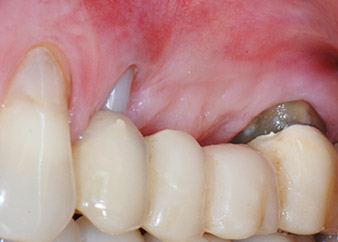

Two-months interim result

Figures 17 and 18 show the clinical result two months after the surgery. Tooth 24 exhibited reduced mobility of Miller class 1, and the soft tissues were free of inflammation. Probing was avoided at this point of time to prevent reinfection and to avoid violating the epithelial attachment. A control visit was scheduled for reentry and placement of healing abutments, six months after the insertion of the implants.

At the two-months recall, the mobility of the remaining “dental element” 24 was already reduced from Miller 2 to Miller 1. The soft tissue attachment was on the level of the neighbouring tooth 23. Moreover, there were no endodontic or periodontal symptoms, so its prognosis may have to be readjusted.

However, as most of the buccal and proximal bone is missing and the composite build-up extends to the apical section of the root, a higher reattachment level is not to be expected due to biologic reasons (Sculean et al., 2008).